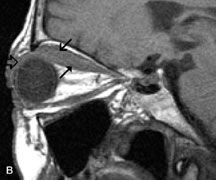

MRI is more effective than CT in delineating the intracranial optic nerves, chiasm, and optic tracts and, for this reason, is the preferred imaging modality in the evaluation of optic nerve disorders. The spatial relationships and image contrast of the orbital tissues with intraorbital optic nerve tumors is comparable between the two imaging modalities. The normal nerve is isointense to brain and appears enlarged and kinked owing to infiltration of an optic nerve glioma on T1-weighted images. Gliomas appear hyperintense on T2-weighted images and may be heterogeneous owing to cystic areas within the tumor. Contrast enhancement is variable.46

Intraorbital and intracranial optic nerve sheath meningiomas are usually isointense to cortical gray matter on Tl-weighted images and remain isointense on proton density studies (Fig. 15). Gd-DTPA is useful in delineating the intracranial extension of optic nerve meningiomas.7,47 The hyperostosis of bone and calcification associated with meningiomas are not demonstrated as well on MRI studies as on CT scans.20,37 Gd-DTPA–enhanced MRI also appears promising in the study of the permeability of the blood–brain barrier in selected optic neuropathies.22,48 MRI may reveal an enlarged optic nerve and some degree of contrast enhancement in cases of optic neuritis.49

Fig. 15. A. T1- and (B) T2-weighted MR scans demonstrate a mass causing fusiform enlargement of the optic nerve sheath complex. The peripheral portion of the mass, representing the meningioma, is isointense to brain on the T1-weighted scan and notably hypointense on the T2-weighted scan. The central portion of the mass, representing an edematous optic nerve, is very hyperintense on the T2-weighted scan (arrow), C and D. Postcontra fat-suppressed T1-weighted scans demonstrate intense peripheral enhancement of the meningioma surrounding the central nonenhancing optic nerve (arrow). Also note the enhancing Intracranial “dural tail” (double arrow).